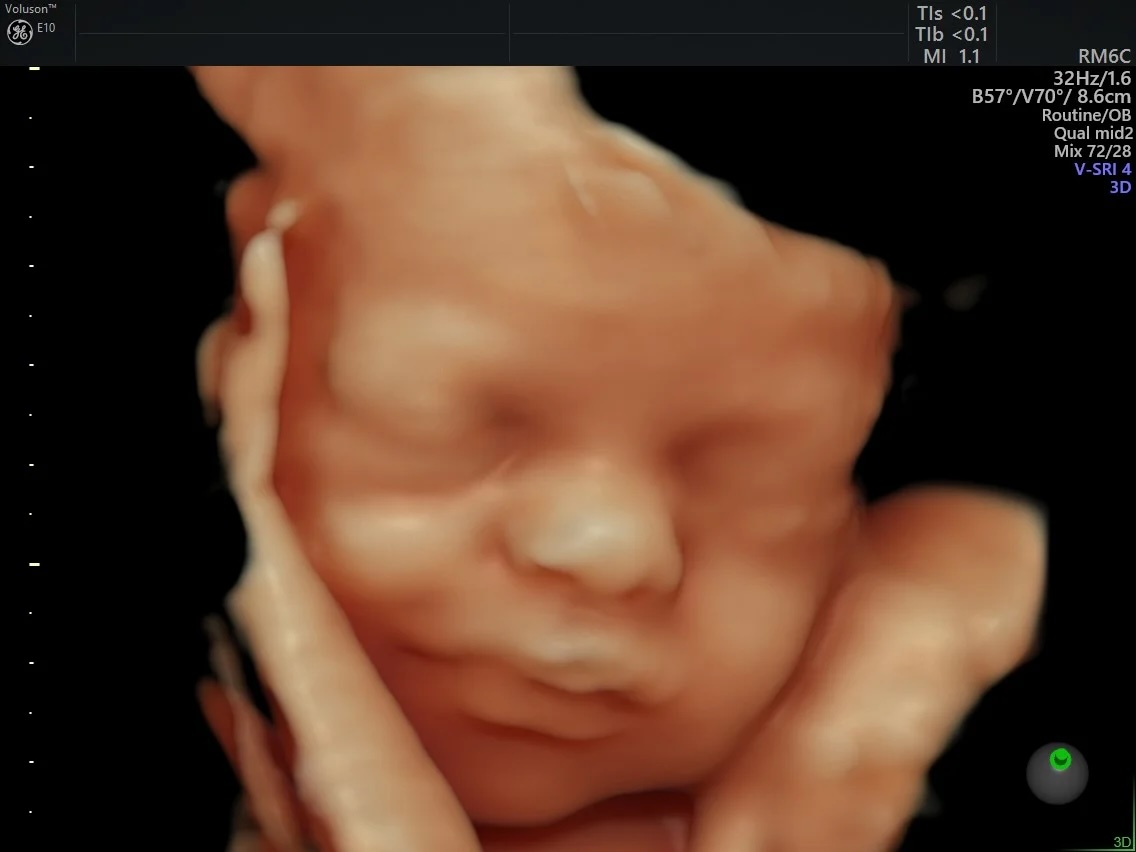

CD Laboratory for Mathematical modelling and simulations for next generations of ultrasound devices (MaMSi)

This CD Laboratory focuses on developing new methods for prenatal ultrasound diagnostics. The long-term goal is to improve the diagnoses of patients who are currently difficult to image. Project Start: 01/2025

FETAL4D

This project aims at developing new preprocessing strategies for in-utero functional MRI with the focus on new high resolution reconstruction and motion correction techniques, quality assessment of preprocessing pipelines and longitudinal analysis of developing functional connectivity in fetuses.